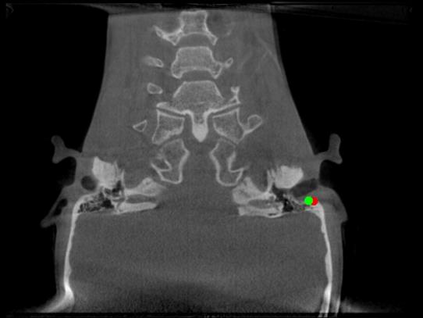

Detecting 3D landmarks on cone-beam computed tomography (CBCT) is crucial to assessing and quantifying the anatomical abnormalities in 3D cephalometric analysis. However, the current methods are time-consuming and suffer from large biases in landmark localization, leading to unreliable diagnosis results. In this work, we propose a novel Structure-Aware Long Short-Term Memory framework (SA-LSTM) for efficient and accurate 3D landmark detection. To reduce the computational burden, SA-LSTM is designed in two stages. It first locates the coarse landmarks via heatmap regression on a down-sampled CBCT volume and then progressively refines landmarks by attentive offset regression using multi-resolution cropped patches. To boost accuracy, SA-LSTM captures global-local dependence among the cropping patches via self-attention. Specifically, a novel graph attention module implicitly encodes the landmark's global structure to rationalize the predicted position. Moreover, a novel attention-gated module recursively filters irrelevant local features and maintains high-confident local predictions for aggregating the final result. Experiments conducted on an in-house dataset and a public dataset show that our method outperforms state-of-the-art methods, achieving 1.64 mm and 2.37 mm average errors, respectively. Furthermore, our method is very efficient, taking only 0.5 seconds for inferring the whole CBCT volume of resolution 768$\times$768$\times$576.